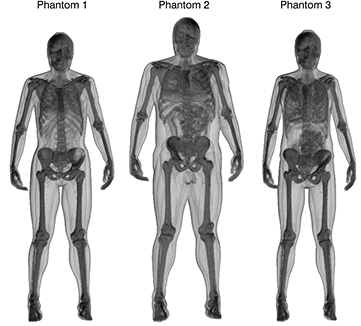

Three adult phantoms with different anatomical characteristics from the XCAT phantom population (Segars et al 2010, 2013) were used in this work. The phantoms are comprised of anatomical templates for different organs, part of organs, various tissues and organ contents (hereafter referred to as phantom structures). The anatomical templates were used in the XCAT computer program to generate three-dimensional (3D) voxel maps where each accessible structure was assigned a unique code integer. This enabled association of each structure to an individual mass density value and time-activity curve, as described earlier (Brolin et al 2013). Mass-density values, required for the simulation of photon and electron transport in the phantom, were obtained from (ICRU 1988). The voxel phantoms were realized with cubic voxels of 2.53 mm3, and the 3D matrix sizes were adjusted to encompass the entire phantom bodies. The phantoms were modified to better mimic typical patients by adding new structures representing tumours. Eight tumours from three different patients were outlined using an in-house developed semi-automatic segmentation program (Gustafsson et al 2012). The tumours were inserted at the approximate locations where originally situated in the patients, i.e. in the liver and abdomen. The properties of the phantoms are summarised in table 1. Their 3D mass density distribution are shown in figure 1, illustrating the different anatomical features.

Figure 1. Volume renderings of the mass density distribution of phantom 1, 2 and 3, illustrating the different body sizes and anatomical features.